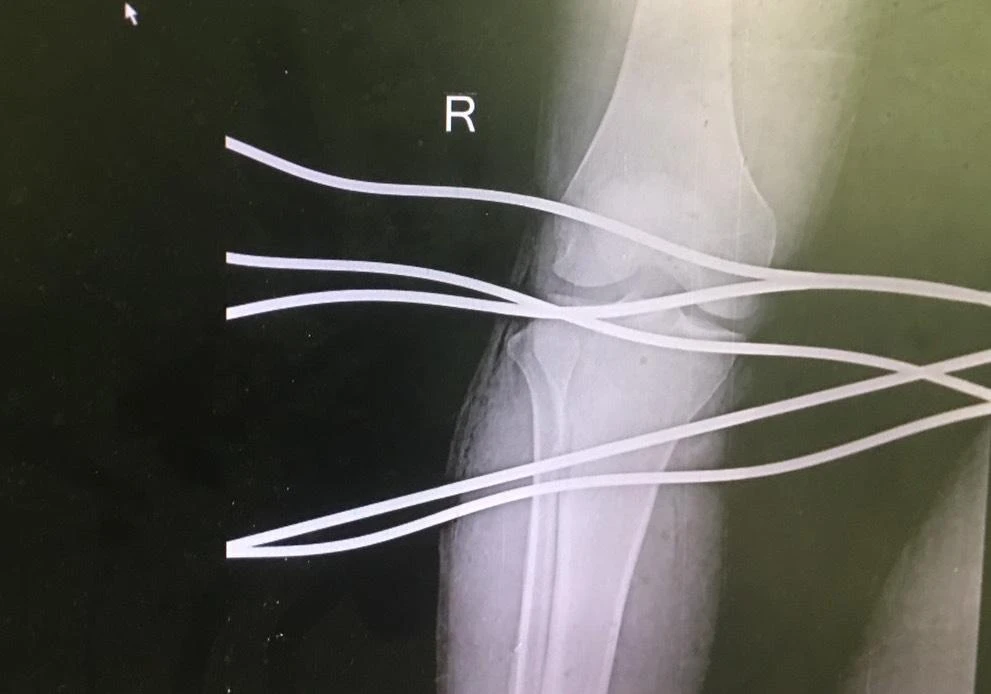

Hình ảnh X-quang bệnh nhân H bị năm thanh sắt đâm xuyên qua chân. |

Trước đó, ngày 4-9, bệnh nhân NTH (19 tuổi, ngụ huyện Sơn Tịnh, Quảng Ngãi) đang kéo cáp bằng máy tại công ty thì bất ngờ dây cáp bị đứt. Năm thanh sắt (dây quấn quanh cáp chịu lực) bung ngược lại, đâm xuyên qua chân.

Sau hơn một giờ, năm thanh sắt đã được lấy ra khỏi chân bệnh nhân. Hiện sức khoẻ bệnh nhân đã ổn định, đang được theo dõi và điều trị tại Khoa ngoại chấn thương.